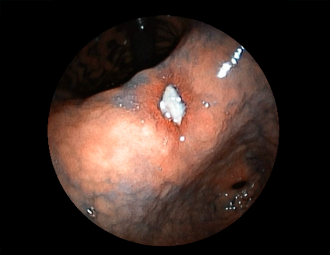

症例1:胃潰瘍(37才、男性)

①胃潰瘍(Stage A1)

健診:胃レントゲン検査で、胃角部ニッシェを指摘され当院受診。

胃角部小弯に、深くて大きな、大きさ約10mmの胃潰瘍(stage 1)

があり、潰瘍底は一部白苔はみ出しを認める。エソメプラゾールマグネシウム水和物投薬で治療開始しました。

(インジゴカルミン散布画像)